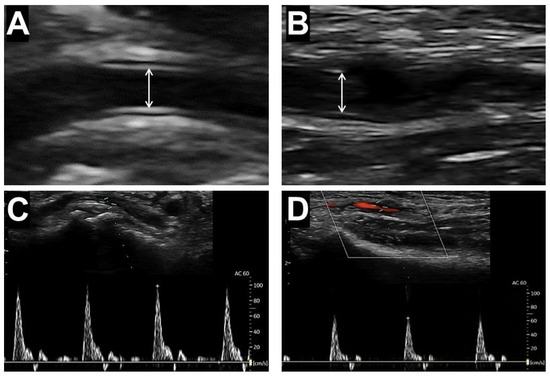

The vessel luminal caliber, defined as the largest distance between the internal hyperechogenic lines of the intima–media complex of the arterial wall in the antero-posterior dimension, was measured during the diastolic phase determined using echo-tracking B-mode ultrasound scanning (Figure 1A,B). The blood peak flow velocities (PFVs) of the arteries were measured at the locations of vessel diameter measurements, using the pulsed-wave Doppler scanner set parallel to the blood flow based on color-Doppler imaging (Figure 1C,D). The values of size and PFV are the averaged results from three consecutive measurements.

Figure 1. Ultrasound measurement of lumen diameters and blood flow velocities in the distal radial artery (A,C) and forearm radial artery (B,D). Arrows indicate the luminal diameter of the artery, measured as the distance between the intimal layers of the intima-media complex.